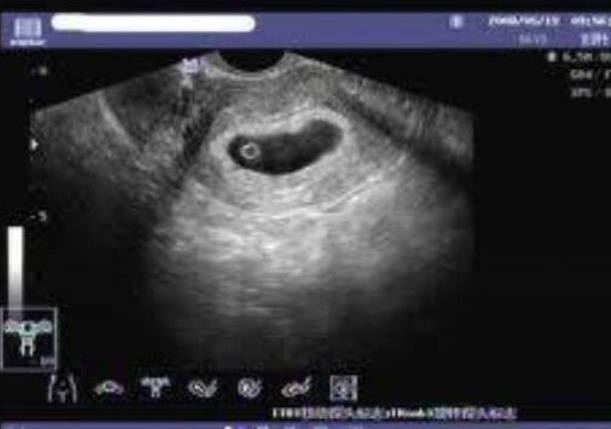

这部分是试管婴儿整个过程中的一个关键过程。因为每个女人的身体状况不同,对药物的反应也不同,所以用药的种类和用量也不同。权威专家会根据每个女性的情况制定合适的促排计划。为了更好地监测促排卵期卵泡的生长发育,还必须按时做b超和抽血检测,及时调整用药,使促排卵达到一定的实际效果。